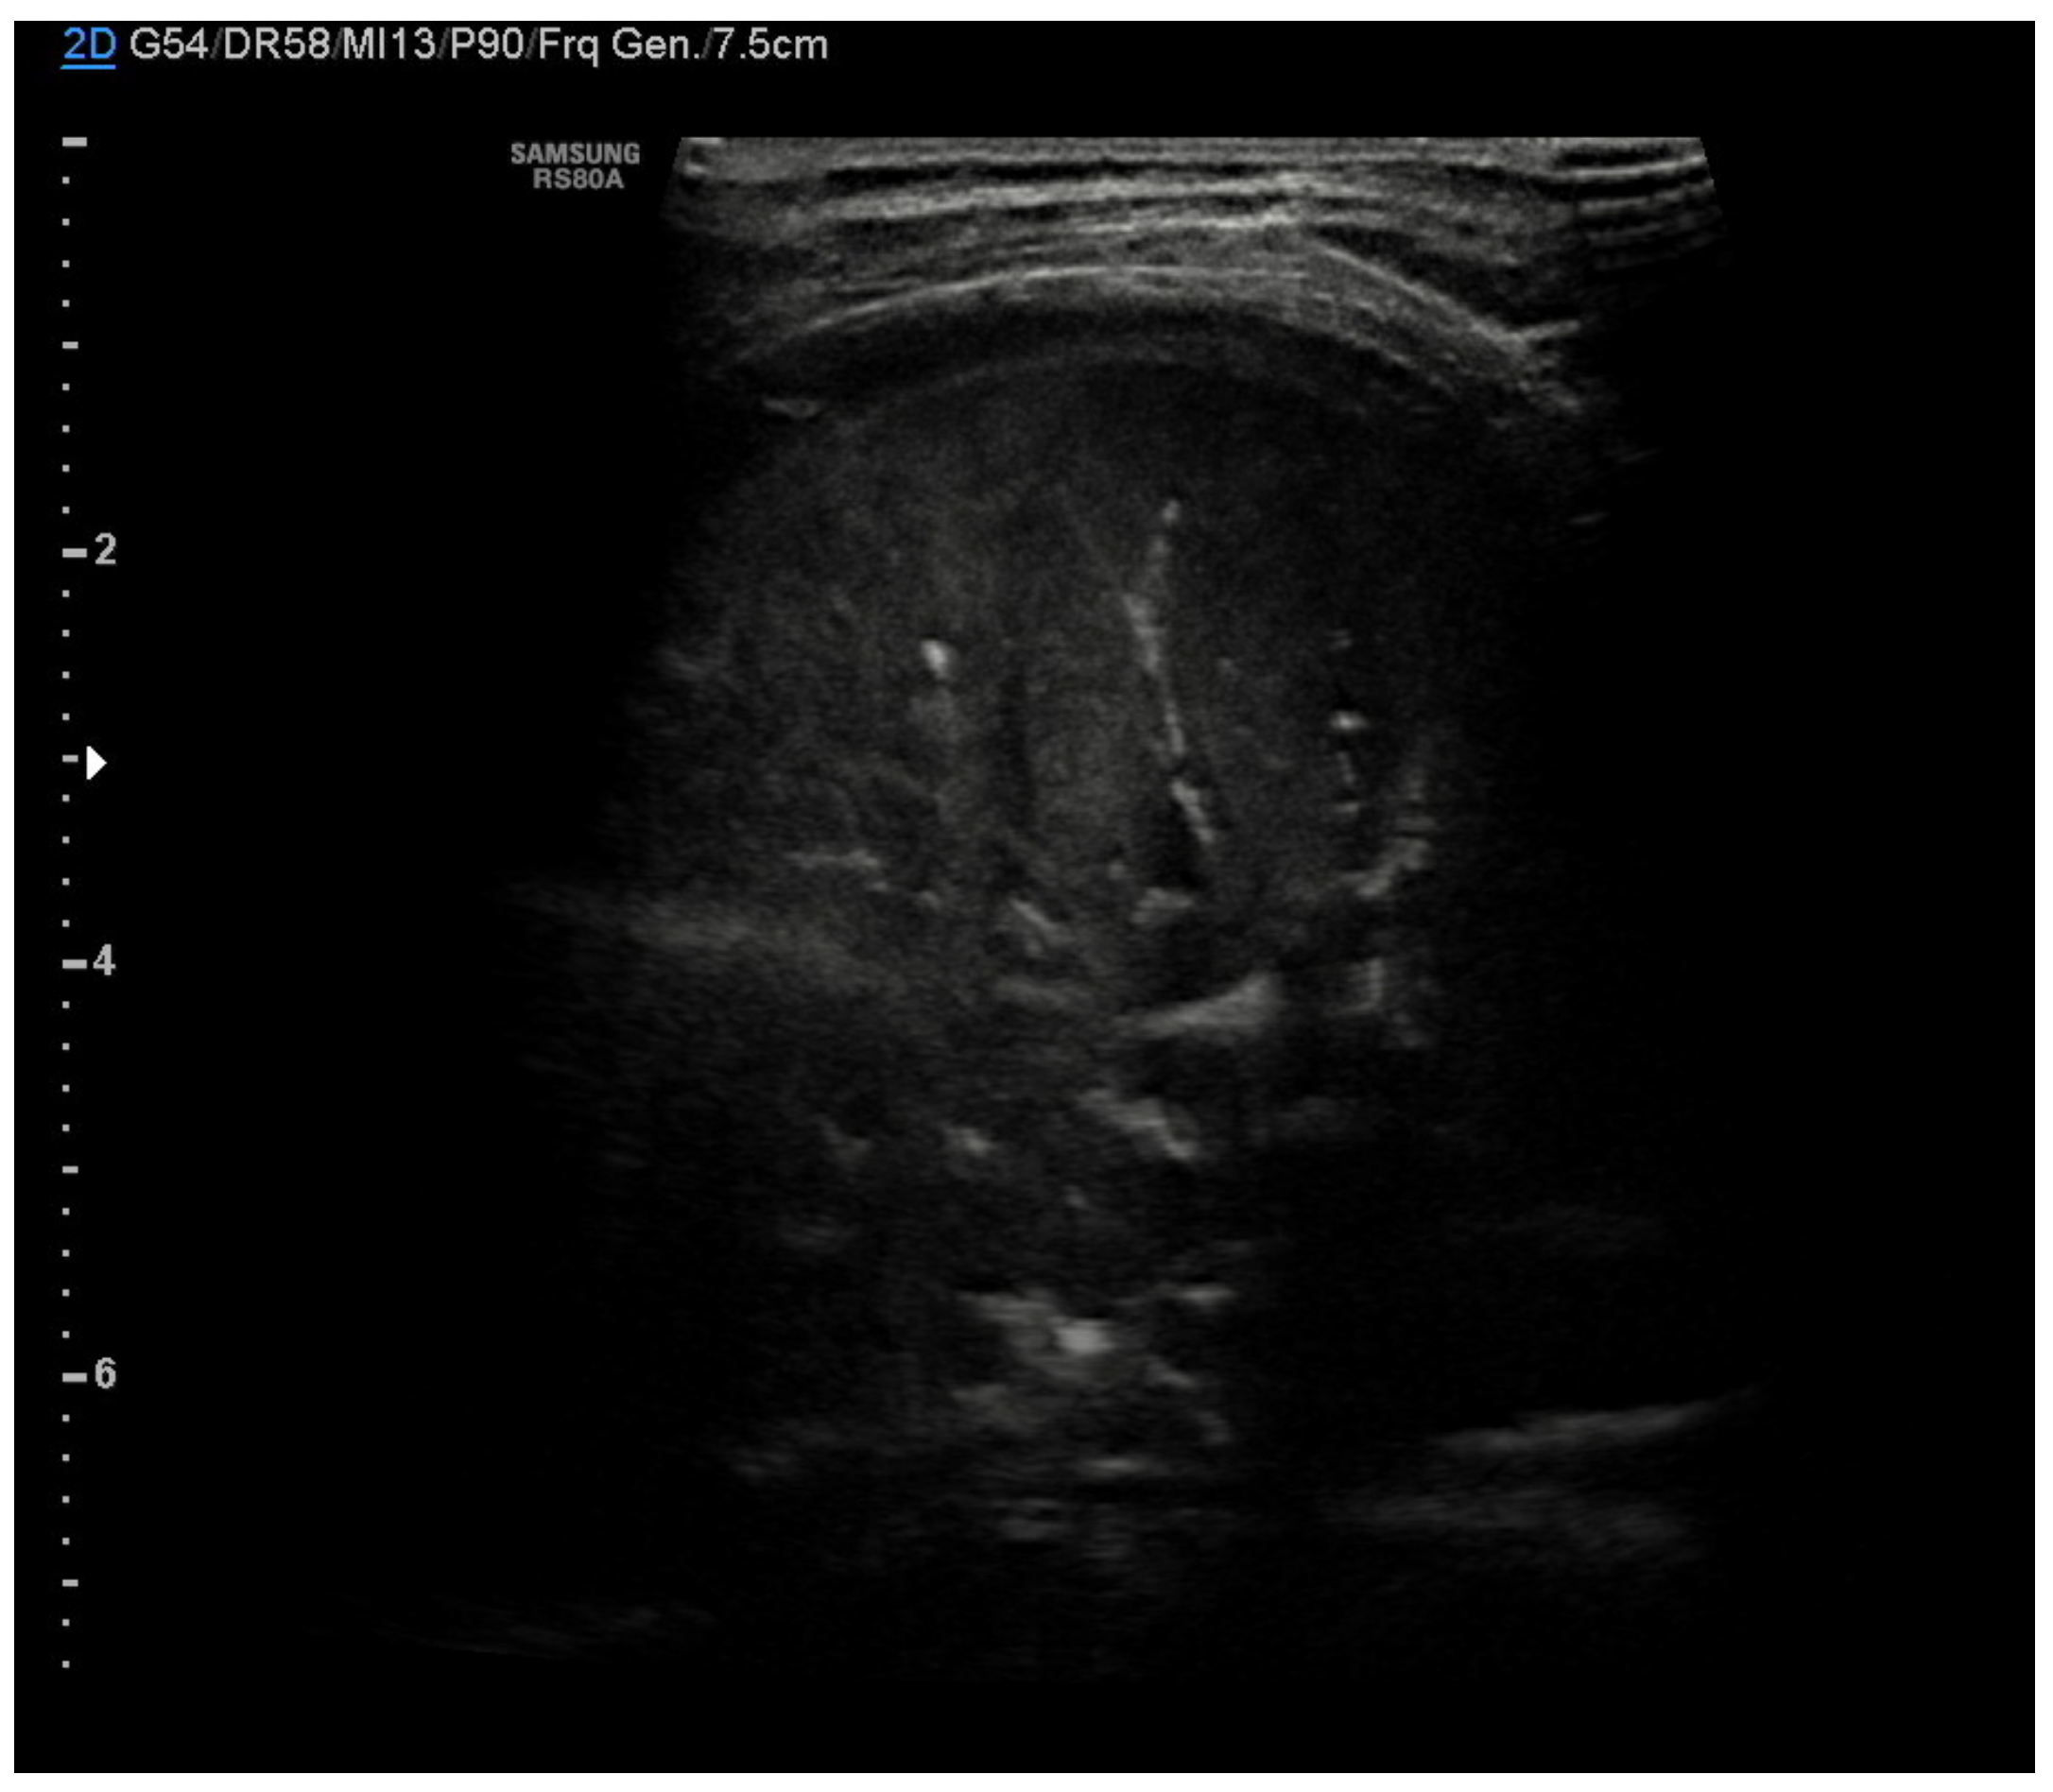

The lung abscess appears as a well-demarcated capsular structure surrounding a hypoechoic core without internal vascularity on color Doppler (Figure 11). Furthermore, it is possible to distinguish lung abscess from pyopneumothorax through the presence of all four specific signs: air-fluid level, synchronous movement of air-fluid levels with breaths, loss of gliding sign above the air-fluid level and the suspended microbubble sign (punctate hyperechoic pinpoints with shadows that move more or less randomly with respiratory movement within the pleural effusion) [56,57].

Figure 11.

Hypoechogenic capsule lesion with irregular, hyperechogenic edges suggestive of lung abscess (white arrow).